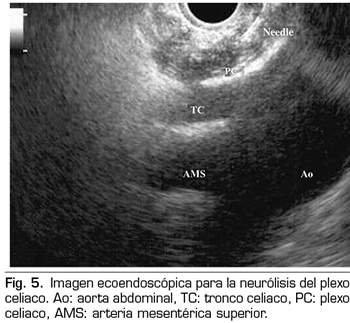

Figura 6